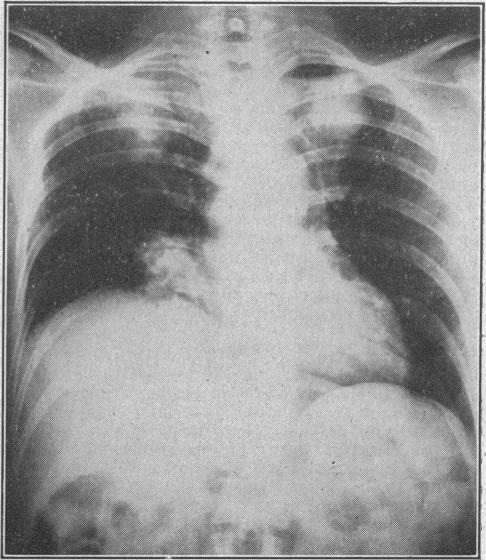

Adrenalectomy for intracranial metastases from carcinoma of the breast.

Br Med J. 1956 Sep 15;2(4993):627-9. doi: 10.1136/bmj.2.4993.627.